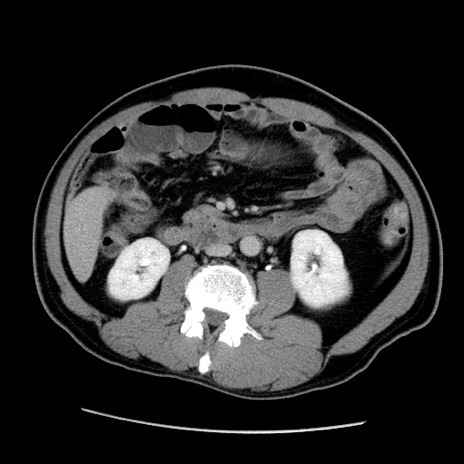

症例22(横断像)

【症例】50歳代男性

【主訴】腹痛

【現病歴】AVMからの被殻出血のため回復期リハ病棟入院中。 本日午後3時頃急に下腹部痛が出現した。

【既往歴】AVM、被殻出血、虫垂炎、高血圧

【身体所見】意識晴明、左半身不全麻痺、会話の理解は良好、36.5°C、腹部:膨隆、全体に板状硬、下腹部正中に圧痛点あり、反跳痛-、筋性防御不明、右下腹部にope scar

【データ】WBC 9400、CRP 0.06